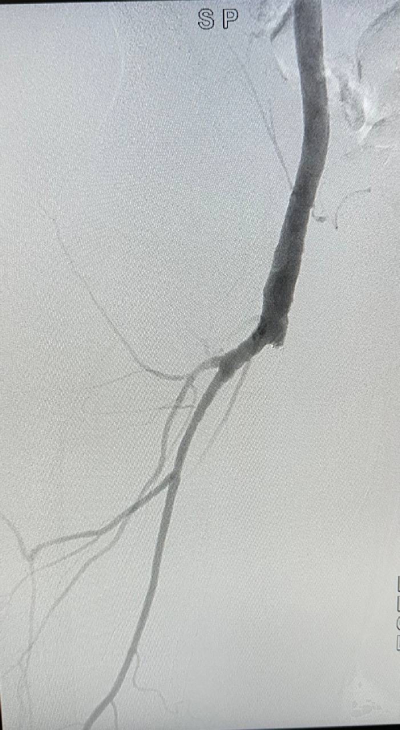

Пациент обратился с жалобами на боли в правой ноге при ходьбе на короткие расстояния и онемение правой стопы в состоянии покоя. В 2019 году мужчине выполнили стентирование поверхностной бедренной артерии справа, однако операция принесла лишь временное облегчение.

Выполнив КТ, врачи отделения обнаружили проблемы с другими артериями, угрожающие здоровью пациента, и приняли решение провести операцию.

Мы использовали инновационные методы — петлевую эндартерэктомию, стентирование и пластику артерий. Выполненные оперативные вмешательства принесли пациенту существенное облегчение.